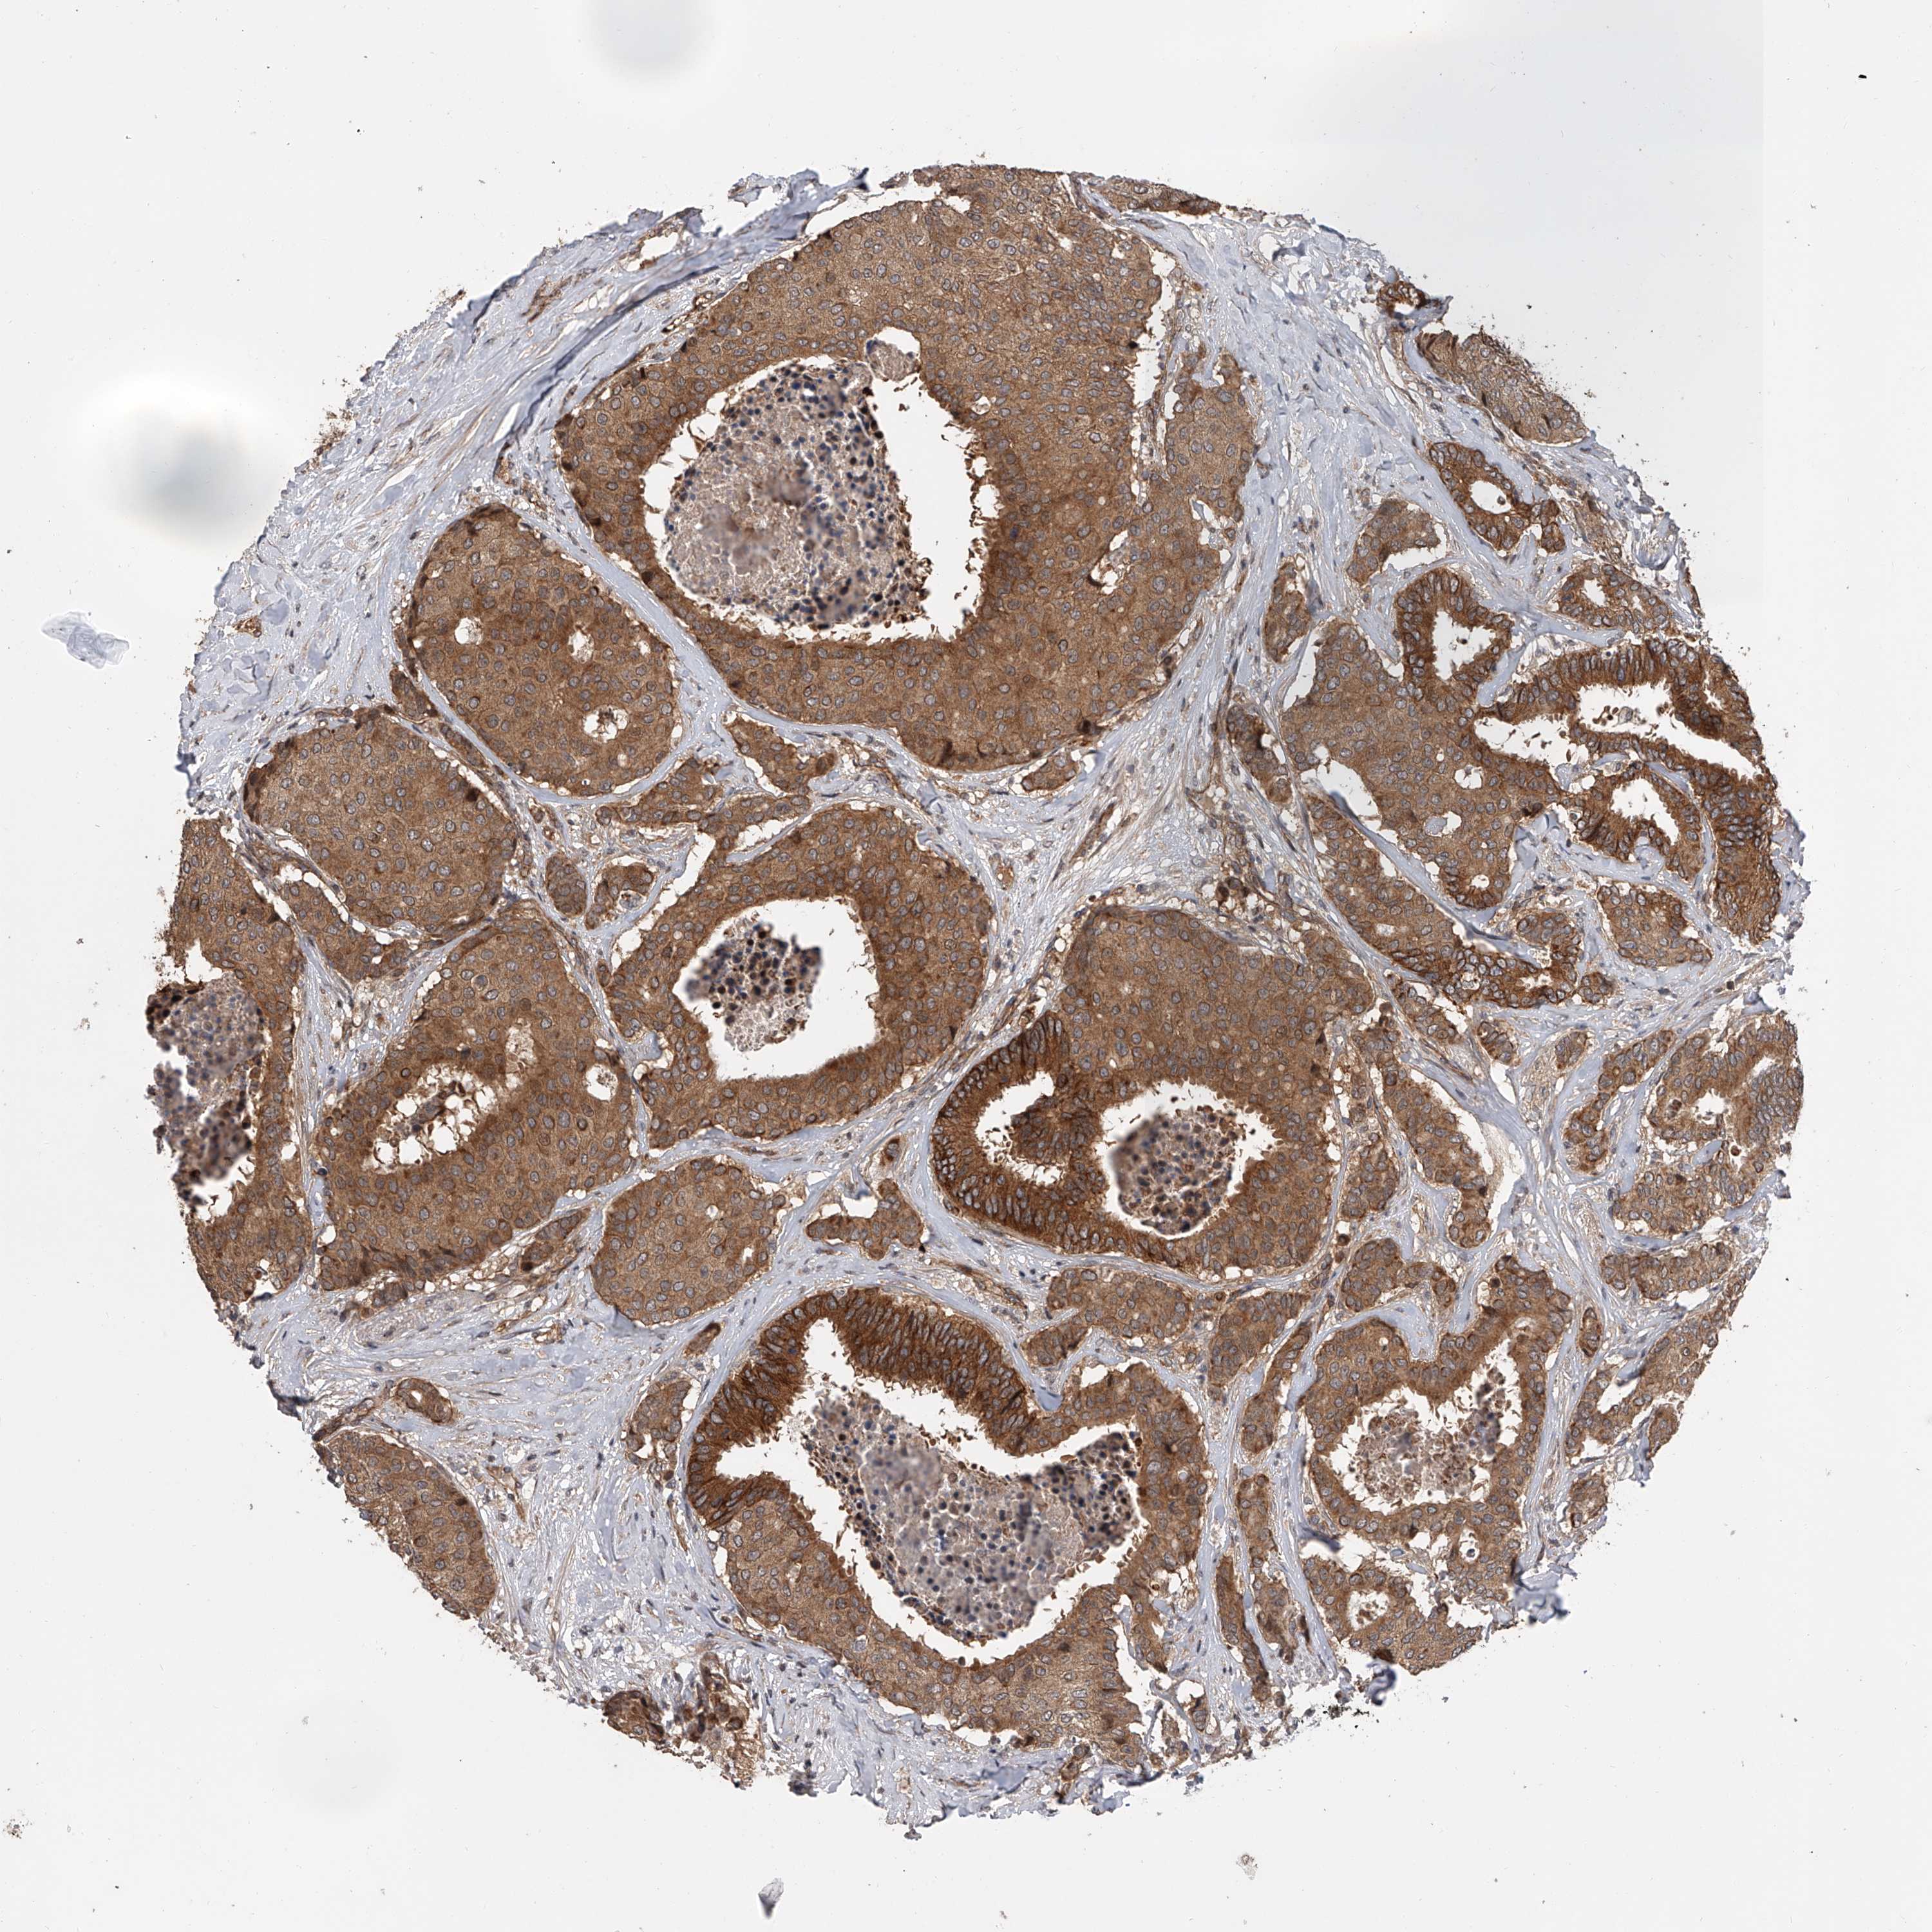

CANCER BREAST CANCER Show tissue menu

BRCA TCGA BRCA VALIDATION PROTEIN EXPRESSION